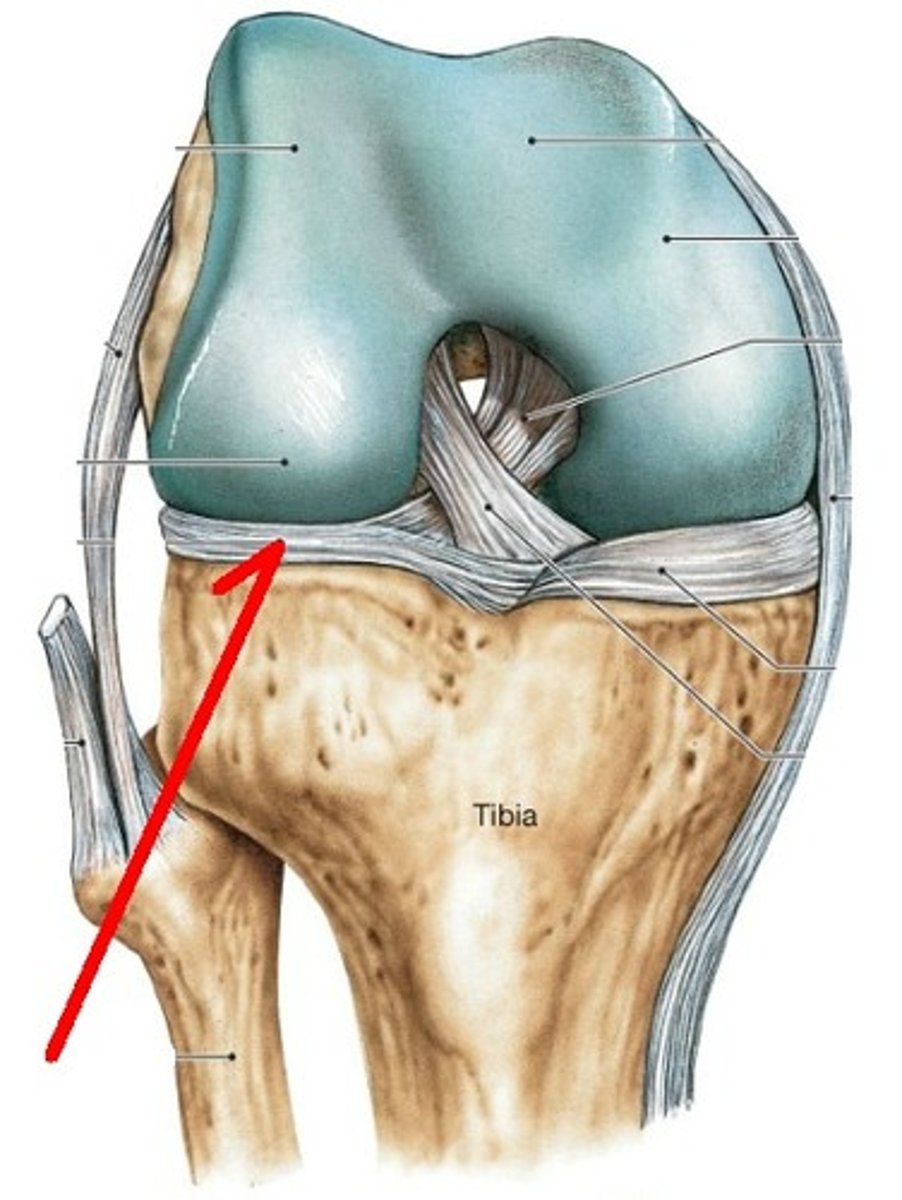

Fibular collateral ligament

Lateral Meniscus

Posterior Cruciate ligament

Tibial Collateral Ligament (MCL)

Anterior Cruciate Ligament (ACL)

Medial Meniscus

Unhappy trio

MCL, ACL, Medial meniscus